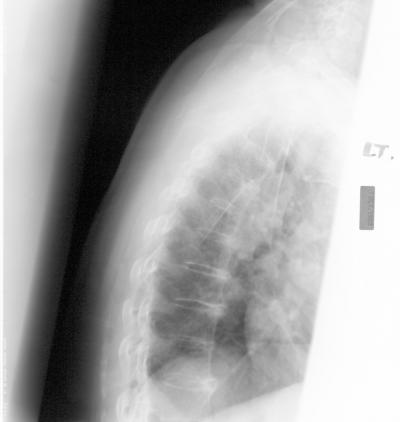

Continuing a popular but controversial treatment for osteoporosis could reduce spine fracture risk for a particular group of patients, but others could see little to no change if they discontinue it. Based on available evidence, a UCSF researcher reevaluated his 2006 finding from a randomized 10-year study of alendronate, a type of bisphosphonate – a class of drugs that prevent loss of bone mass.

Osteoporosis is responsible for 1.5 million fractures in the United States a year at a cost of $14 billion annually. As many as half of all women and a quarter of men older than 50 will break a bone due to osteoporosis, according to the National Institutes of Health.

The original study by Black and colleagues studied a total of 6,459 women for up to five years, comparing alendronate to a placebo. That study showed less fracture risk of spine, hip and other major bones and led to FDA approval of alendronate in 1997. In a newer 2006 continuation study, 1,099 of the women who had taken alendronate for an average of five years at the start of the continuation study were randomly assigned to five more years of alendronate or a placebo. Those who continued on alendronate showed lower risk of spine fractures but no difference in risk for non-spine and hip fractures.